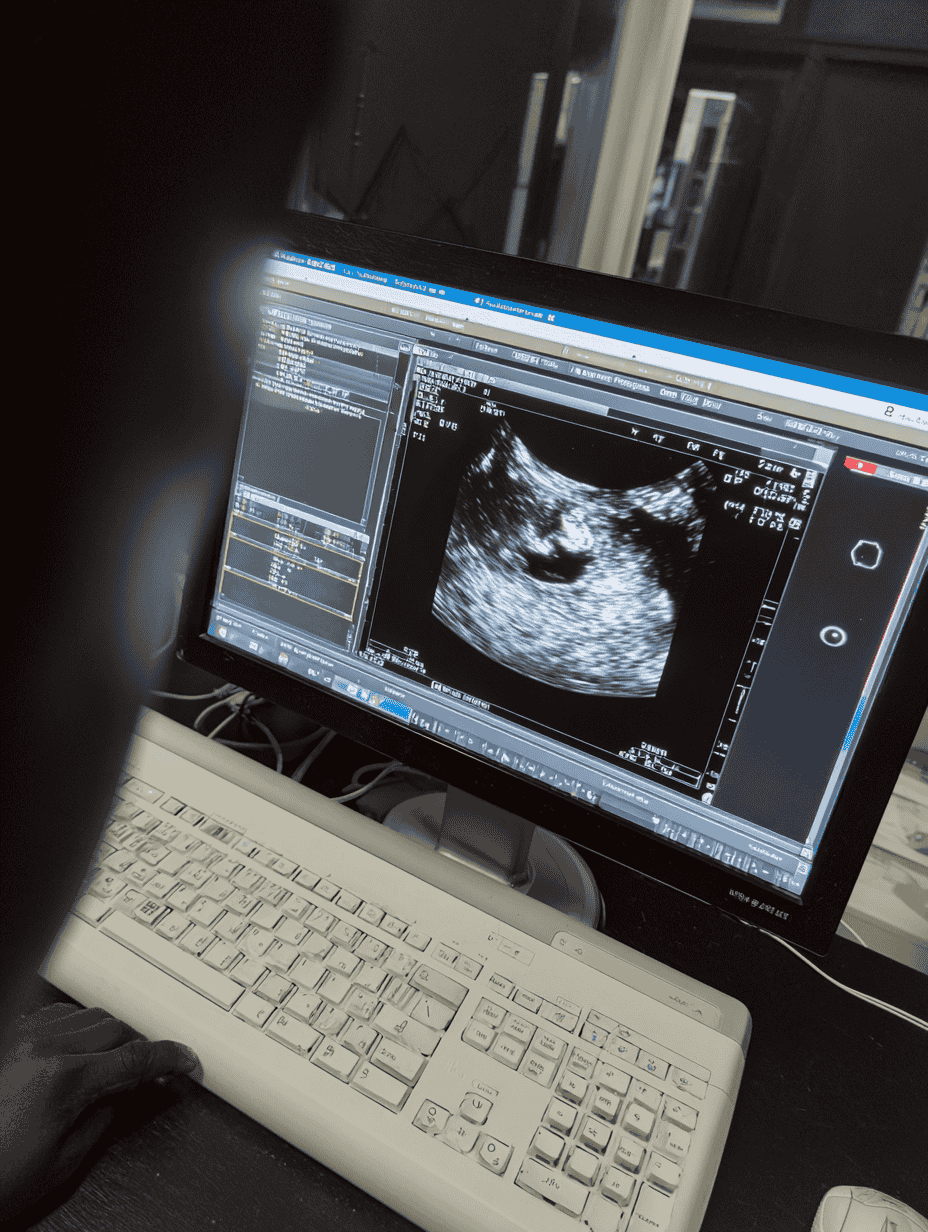

In certain cases, additional imaging (liver ultrasound or magnetic cholangiography) is recommended for a complete assessment of the liver’s morphology and function.

- Liver ultrasound / elastography to assess fibrosis